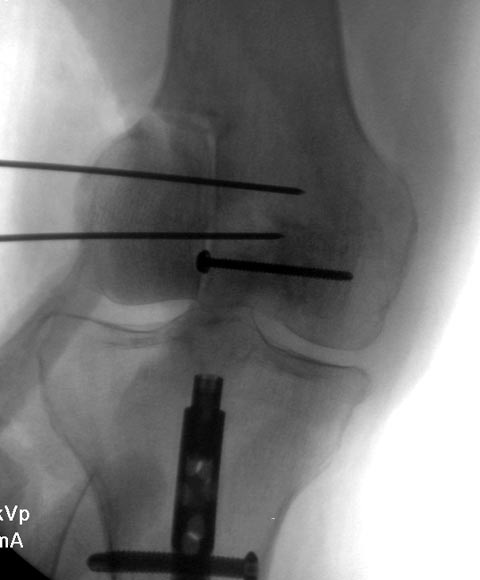

Здесь представлен посттравматический дефект латерального мыщелка и

лечение аллографтом.

Вложение не в текстовом формате было извлечено…

Имя     : Medial Tibial plateau 5.jpg

Тип     : image/jpeg

Размер  : 33096 байтов

Описание: отсутствует

Url     : http://weborto.net:8080/pipermail/ortho/attachments/20141113/94e46382/attachment-0006.jpg